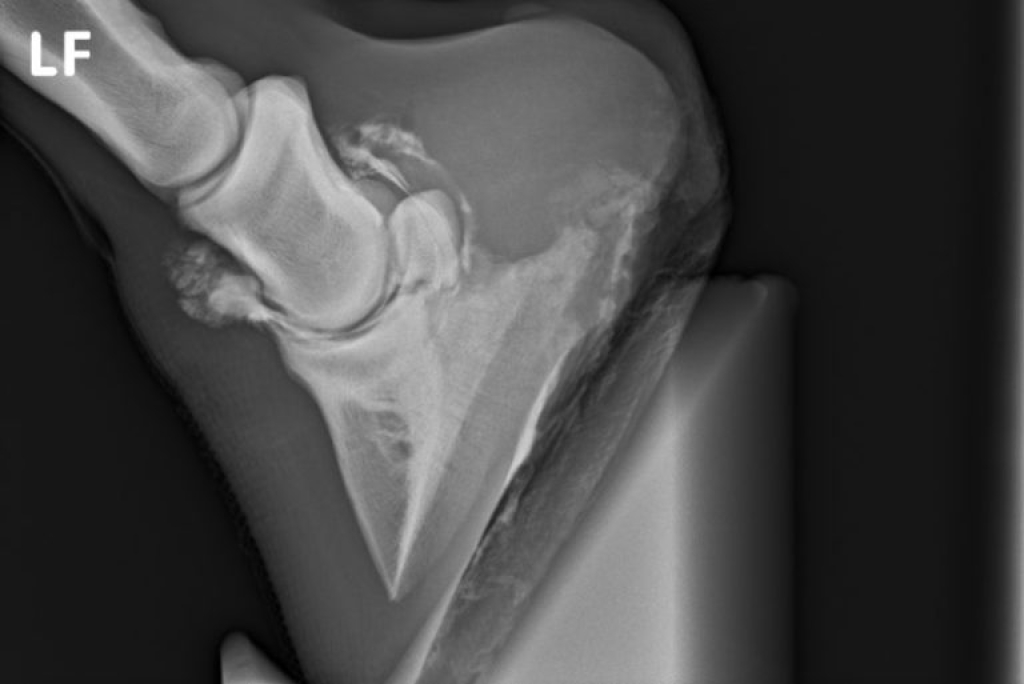

Röntgenopname van een slijmbeurs na injectie met contrast medium.